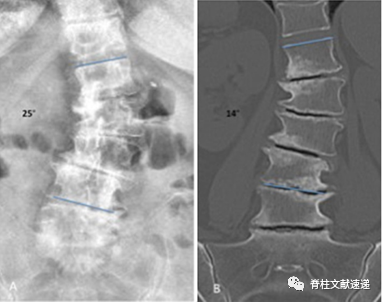

患者术前需完善影像学检查(X线、CT、MRI)。X线可显示站立和卧位时椎间盘高度存在明显差异,CT结果中同样可以观察到这种现象,站立和卧位时X线及CT结果显示椎间隙高度变化的情况称之为手风琴现象(如下图),提示椎体存在不稳定情况。

MRI检查同样是必须的,MRI检查可以排除骨折、感染、转移性肿瘤等病理情况。同时可以观察到患者椎间盘是否存在真空征(当椎间盘发生退变,椎间盘内的髓核就会萎缩、坏死,从而椎间盘内就会出现裂隙,产生负压,周围血液内或者是组织内的气体,比如N2或者CO2就会进入裂隙当中,在X线片或CT的影像结果上就会出现低密度影,这就是真空征),这是一种椎间盘的退行性病变。观察到真空征是实施PCD所需的一个重要条件,骨水泥主要填充该部分空间。

图注:图A为站立位X线结果,图B为卧位CT结果,椎间塌陷导致不同的Cobb角度(分别为25°和14°),该现象即为手风琴现象。